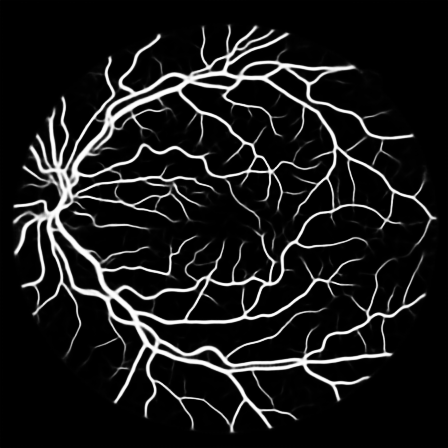

Fig. 2: An example from the DRIVE dataset. Stratification (first row, left to right): (1) input image, (2) raw mask, (3) stem mask, (4) thin mask; Segmentation Results (second row): (5) overall prediction (red are false positive area while green are false negative area), (6) raw prediction, (7) stem prediction, (8) thin prediction (of the Ngsubscript𝑁𝑔N_{g} stream)

To justify the performance of our model, we compare the 4 metrics with 8 representative previous works from all 3 open-access datasets. The comparison results presented in Table 1 show that our MP-Net model outperforms the state-of-the-art methods regarding accuracy and AUC𝐴𝑈𝐶AUC in all three datasets, which meter the practical prediction quality and the overall prediction quality independent on thresholding specifications. The AUC𝐴𝑈𝐶AUC advancement is greater in the DRIVE dataset. It’s related to the fact that the DRIVE dataset contains more thin vessels, which is the main target of our model. Specificity is also the highest in DRIVE and CHASE_DB1 while sensitivity is highest in STARE. Particularly, our method outperforms ML-UNet [2] and JL-UNet [4] which adopt a different multi-class approach to also especially tackle the thin-vessels challenge. Figure 2 shows an example of our segmentation maps on DRIVE. As can be seen, most thin vessels and boundary areas have been meticulously picked up.